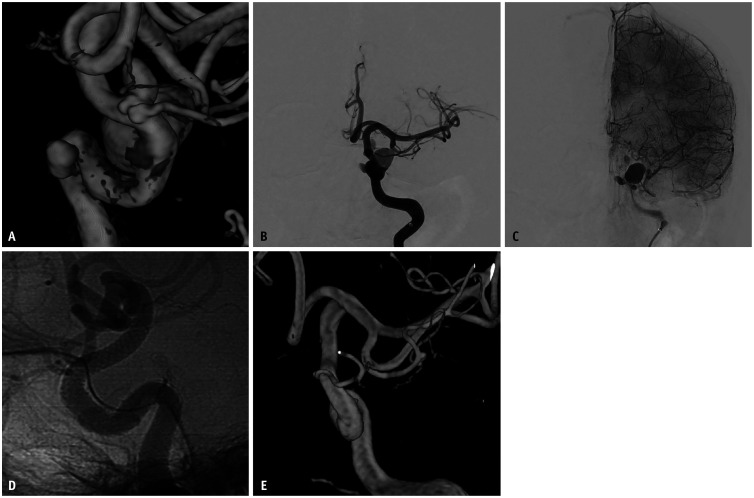

Abstract Image